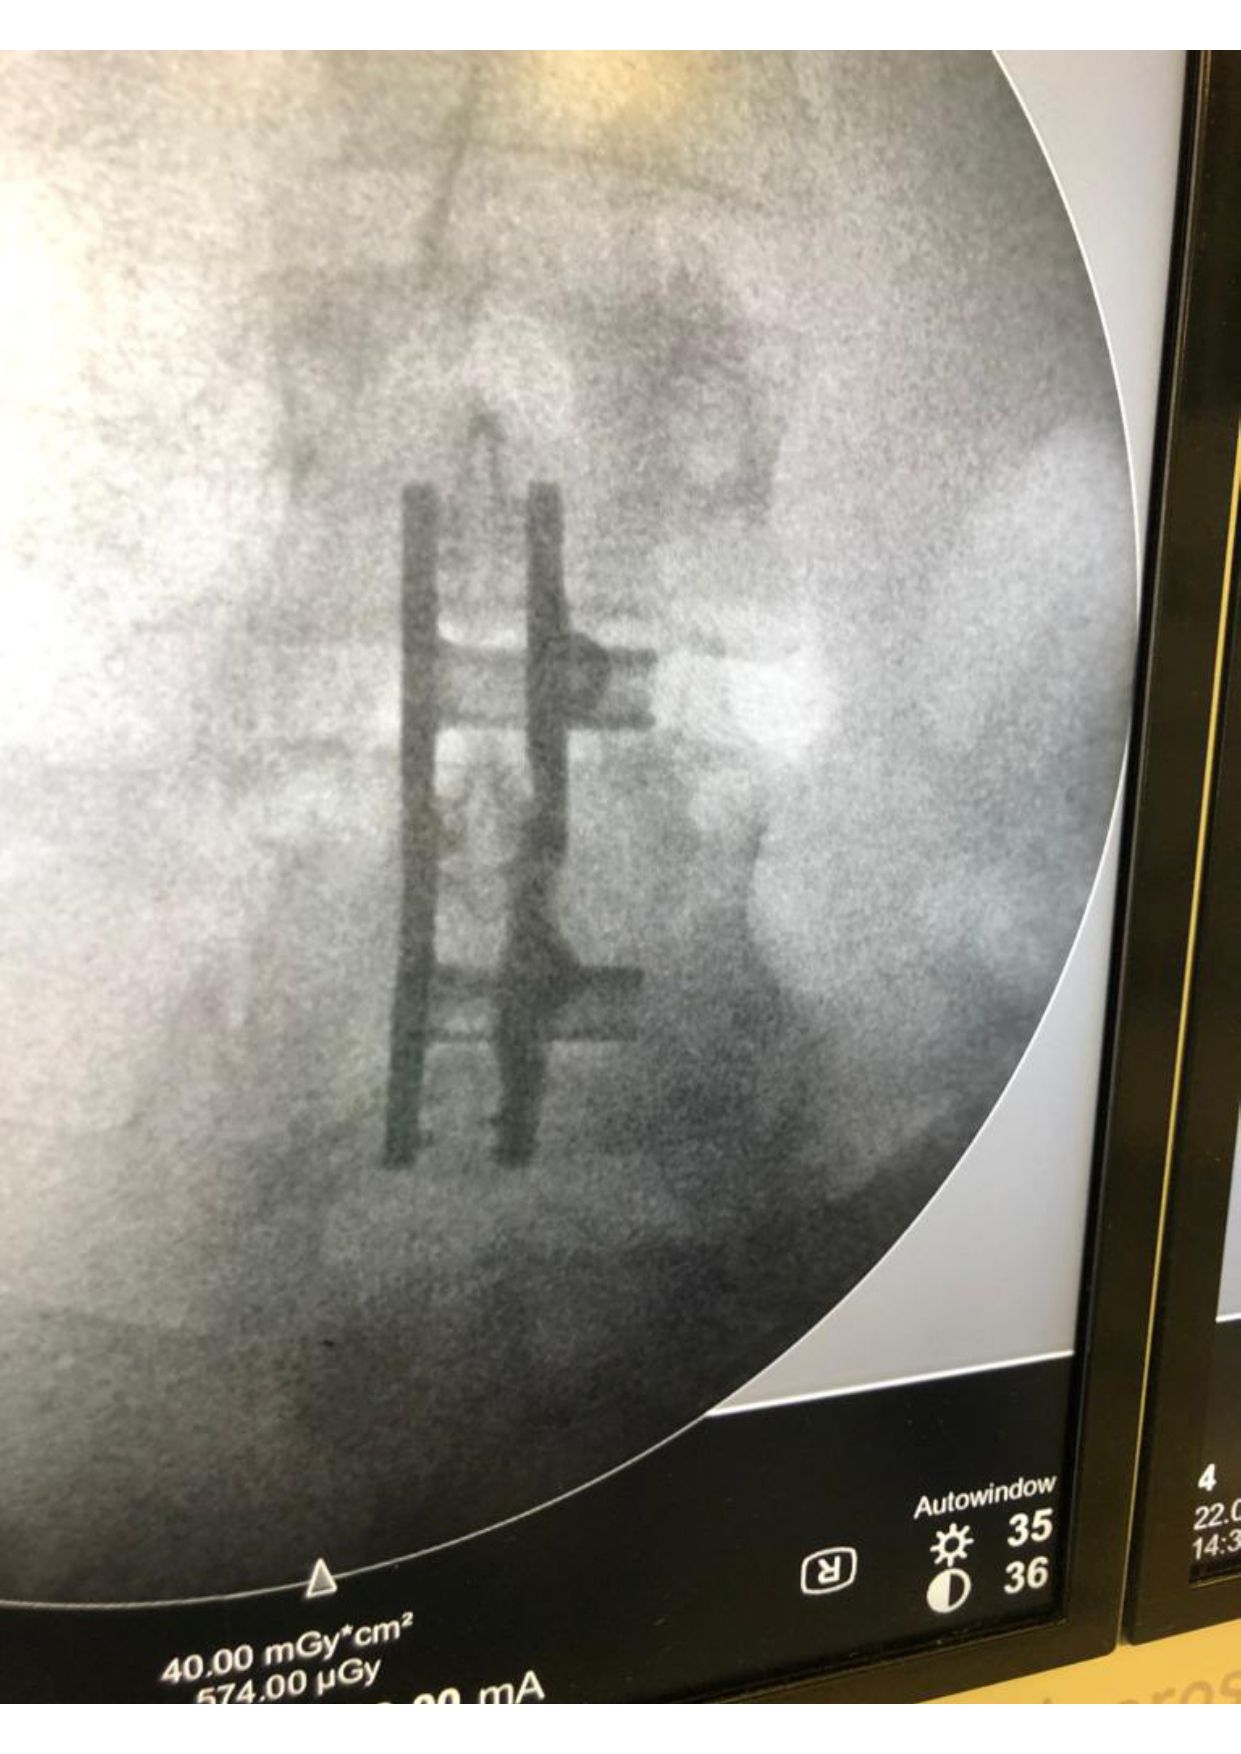

Patologia Degenerativa da Coluna Vertebral

- Tratamento de doenças que afetam a estrutura e função da coluna, com potencial impacto na qualidade de vida.